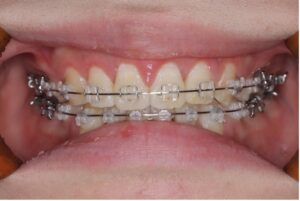

上の歯は裏側、下の歯は表側に装置をつけるワイヤー矯正です。

笑ったときに見えやすい上の歯は裏側にすることで見た目への影響を抑えることができます。

上の裏側についてる装置が舌に触れるため慣れるまで発音に違和感はありますが、フルリンガル(上下裏側)に比べると影響は少ないです。

〈メリット〉

・正面から見た時に装置が目立ちにくい

・フルリンガルより費用が抑えられる

・舌への違和感が比較的少ない

〈デメリット〉

・下の歯の装置は見える

・装置装着後は違和感を感じやすい